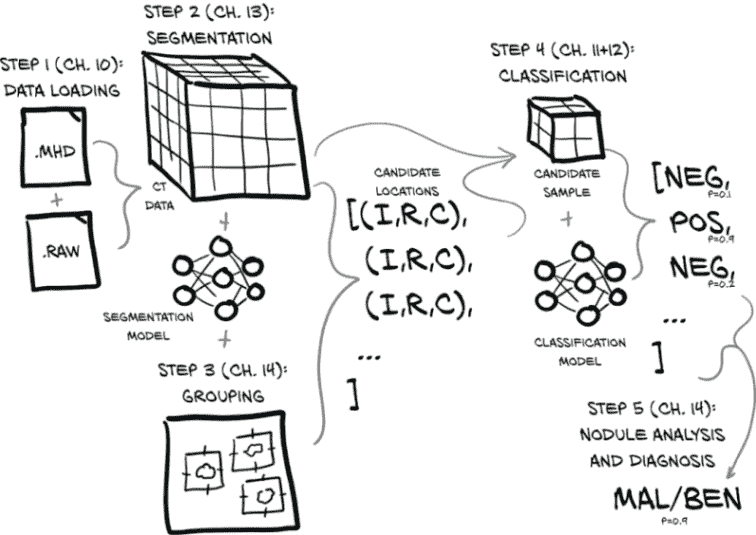

我们在图 9.4 中展示的完整端到端解决方案将加载 CT 数据文件以生成包含完整 3D 扫描的Ct实例,将其与执行分割(标记感兴趣的体素)的模块结合,然后将有趣的体素分组成小块,以寻找候选结节。

图 9.4 完整胸部 CT 扫描并确定患者是否患有恶性肿瘤的端到端过程

结节位置与 CT 体素数据结合,产生结节候选,然后可以由我们的结节分类模型检查它们是否实际上是结节,最终是否是恶性的。后一项任务特别困难,因为恶性可能仅从 CT 成像中无法明显看出,但我们将看看我们能走多远。最后,每个单独的结节分类可以组合成整体患者诊断。

更详细地说,我们将执行以下操作:

图 9.4 仅描述了在构建和训练所有必要模型后通过系统的最终路径。训练相关模型所需的实际工作将在我们接近实施每个步骤时详细说明。

让我们在图 9.7 中重复我们的高层概述。

图 9.7 完成全胸 CT 扫描并确定患者是否患有恶性肿瘤的端到端过程